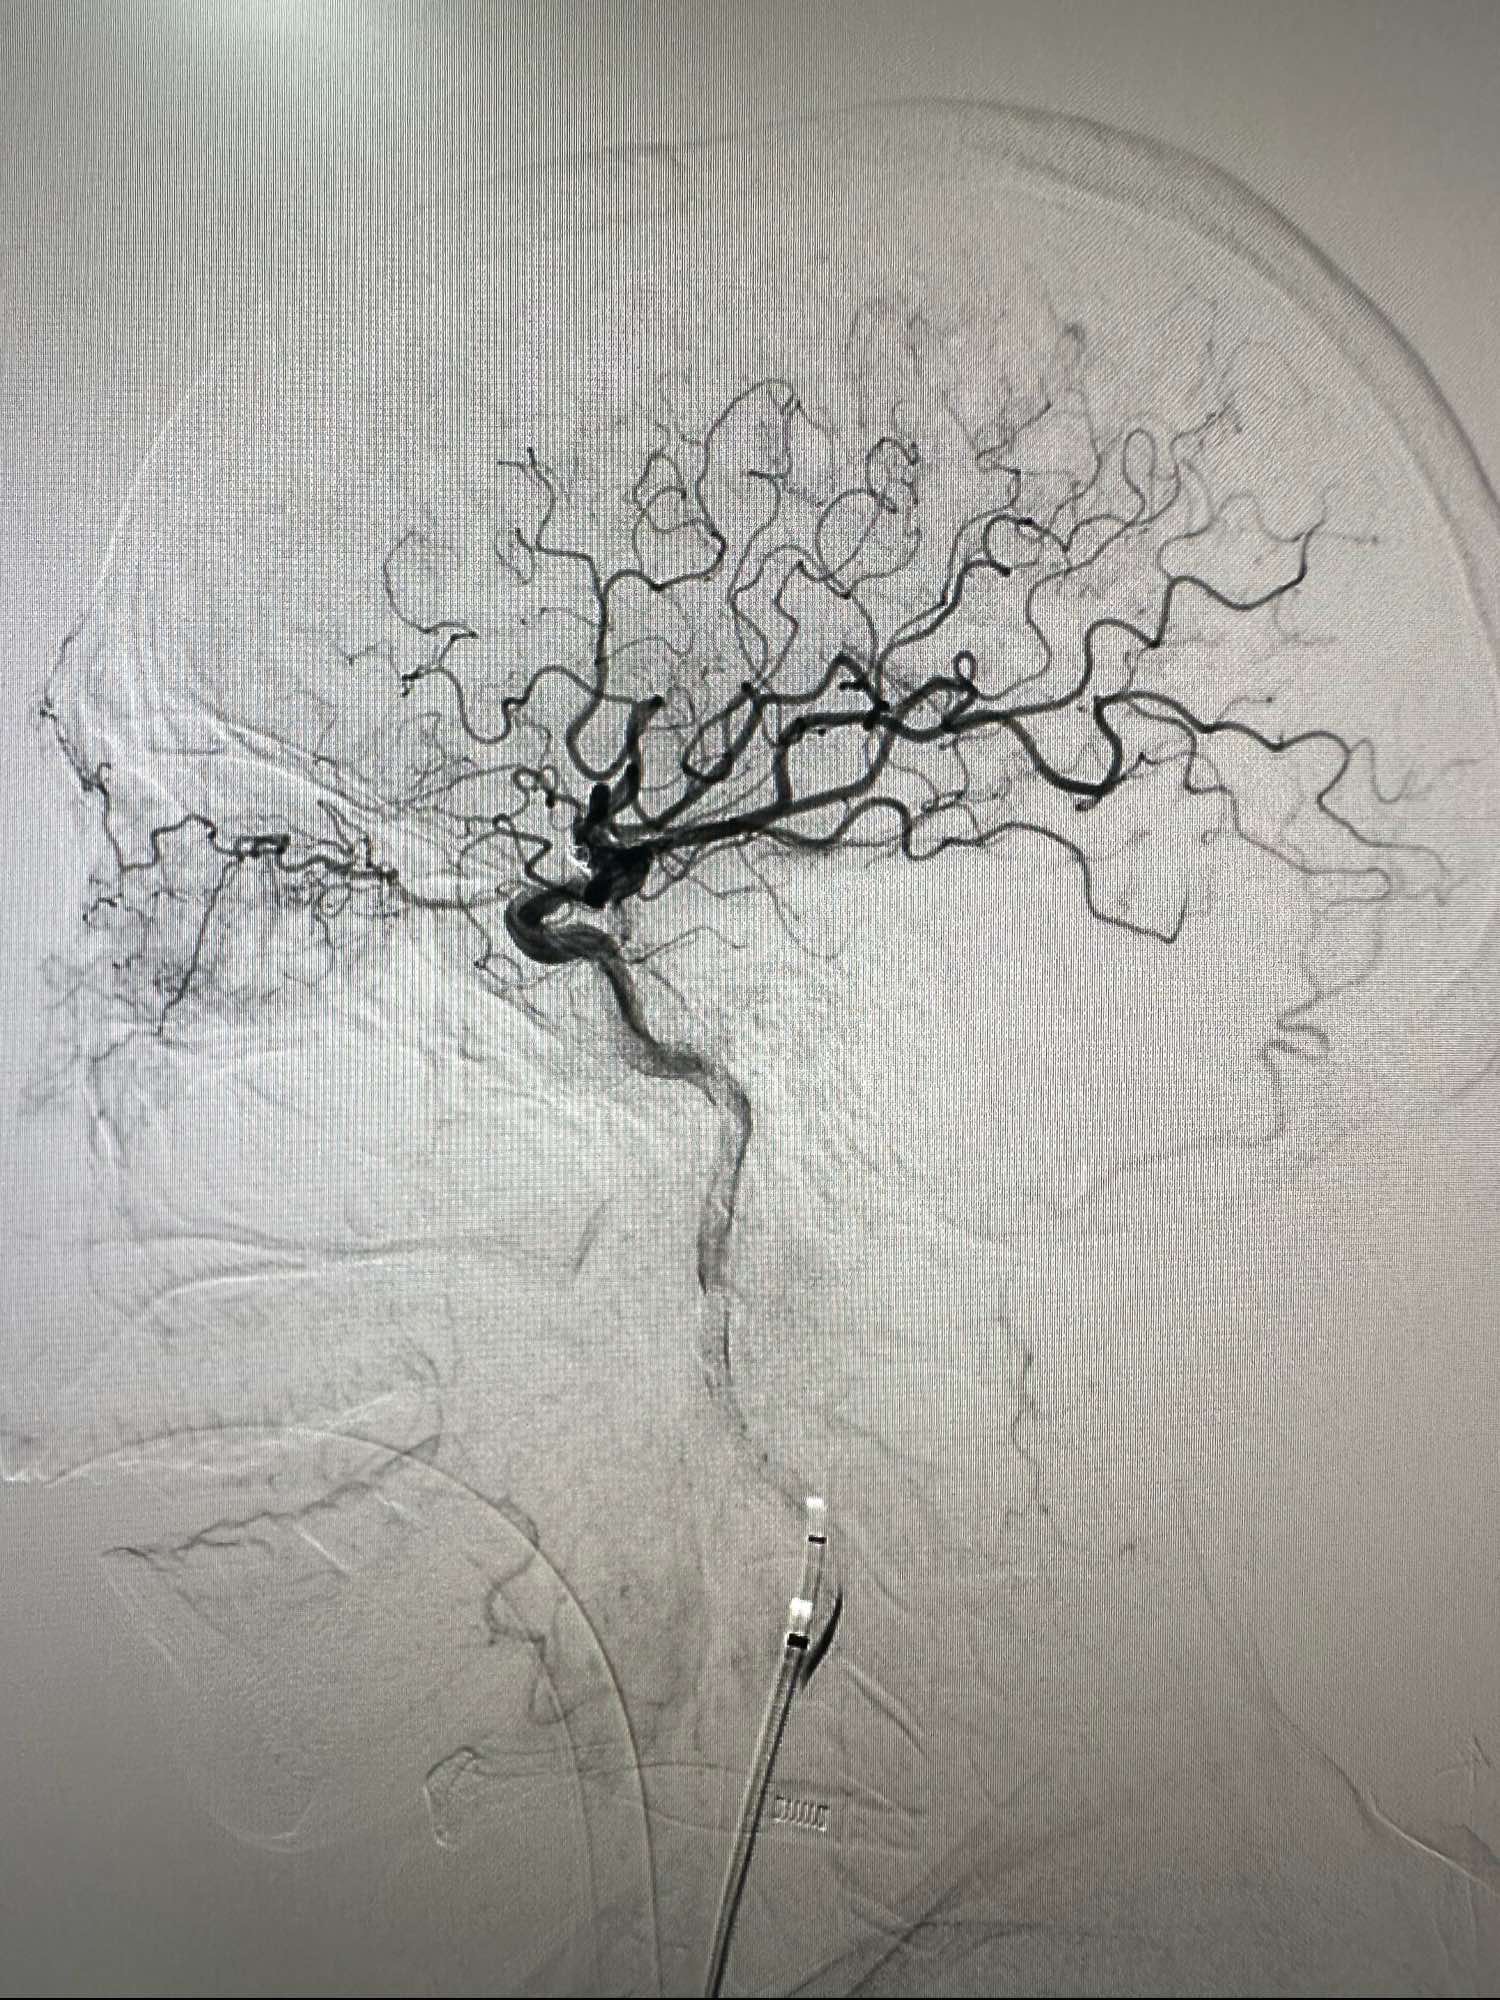

右侧颈内动脉造影正位

考虑牛角弓

左侧颈内动脉造影正位

侧位